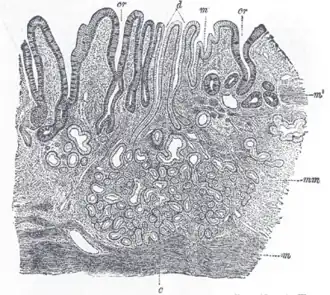

Sección de la membrana mucosa del estómago humano, próxima al orificio del Cardias. X 45 (ampliado 45 veces).